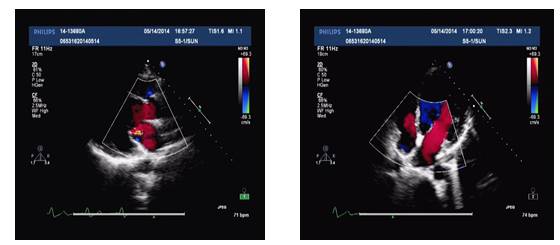

UCG(2014-5-14):

◆IVS 0.86cm, LVDd 6.4cm, EF 40%

◆轻-中度二尖瓣关闭不全

◆UCG: LVDd 5.7cm, LAD3.9cm, LVEF 50%, 轻中度二闭

◆UCG: LVDd 5.6cm, LVEF 53%

◆UCG: LVDd 5.65cm, LAD3.9cm, LVEF: 50%